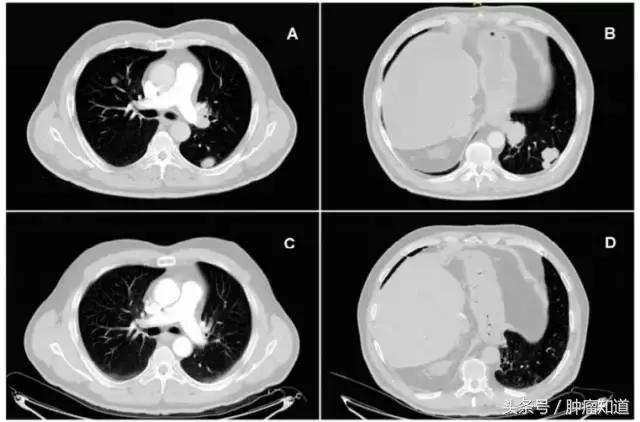

鉴于对肝移植后出现复发转移的患者没有多少治疗方案,医生对患者尝试用Pembolizumab(Keytruda)治疗,治疗剂量为:200mg,每3周一次,同时继续索拉非尼治疗。结果,患者对Keytruda反应非常好,没有出现任何不良反应或者移植排斥反应,肝功能也没有出现紊乱。3个月后,患者对Keytruda反应仍然良好,影像学检查显示,肿瘤已经完全消失。(如下图所示)

▲ 这个图为胸部CT扫描片:A 、B为Keytruda治疗之前的情况,可以看出肺部有多个病灶,说明肿瘤有转移。C、D为Keytruda治疗3个月时的情况,可以看出转移灶已完全消失 。